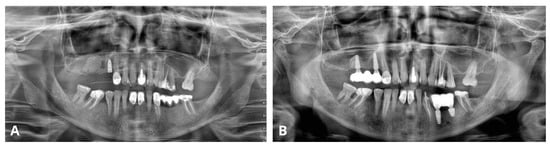

2.1. Case 1—Primary Version

This case sets a proper example of the primary version of the CET that has been conducted on a patient qualified for open sinus lift before implant placement in positions 16 and 15 (FDI numbering system) (Figure 1A,B). CBCT unveiled a homogeneous “dome-shaped”/“rising sun” solitary radiopaque mass located at the floor of the right maxillary sinus, precisely above the region of the planned sinus lift (Figure 1C). The radiological image, class III B by Di Girolamo classification [6], combined with the absence of symptoms, suggested a mucous retention cyst or pseudocyst of the maxillary antrum [2]. Although in such cases, Di Girolamo et al. suggest endonasal sinus surgery (ESS) before sinus lift due to possible difficulty in sinus floor elevation and risk of ostium obstruction, our article provides a solution to avoid ESS and prolonged treatment without compromising the sinus lift procedure and the final outcome.

Figure 1. Clinical situation before the surgery. Occlusal view (A), lateral view (B), and CBCT scans with a dome-shaped radiopaque lesion in the sinus and insufficient bone height that requires sinus lift before placing implants (C).